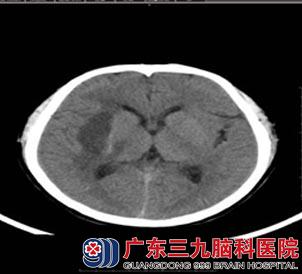

噩运还是降临在邓先生身上,在今年5月份,正在上班的他突然出现头胀、左侧肢体无力,左上肢不能抬举,左下肢不能行走,立即送到当地医院门诊测血压:200/140mmhg,行头颅CT示右侧基底节区脑出血,给予药物治疗效果差。病情进行性加重,治疗后邓先生仍感到头胀,并出现眼胀及嗜睡,为进一步诊治来到广东三九脑科医院脑血管病诊疗中心(神经内二科)就诊,王展航主任以“脑出血”将其收住入院。

入院头颅CTA示所示右侧椎动脉细小,以V4段明显,考虑发育变异,右侧基底节区血肿区未见明显异常血管影。头颅CT示右侧基底节区脑出血,量约18ml,右侧大脑镰下疝。

神经内二科王展航主任指示给予脱水药物脱水降颅压,营养脑细胞,稳定血压,保持水电解质平衡等对症治疗。 经过一个月左右的药物治疗及康复治疗,右侧基底节区脑出血明显吸收缩小。出院时,邓先生可以独立行走,上肢动作也比较灵活。